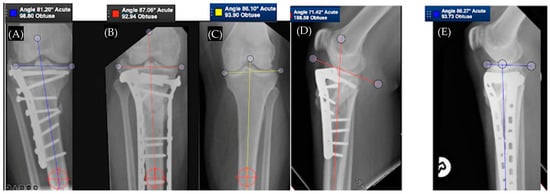

3.2. Tibial Plateau Malunion

3.2.2. Lateral Plateau

3.2.3. Medial Plateau

3.2.4. Posteromedial Plateau

3.2.5. Bicondylar Plateau

3.2.6. Plateau Widening